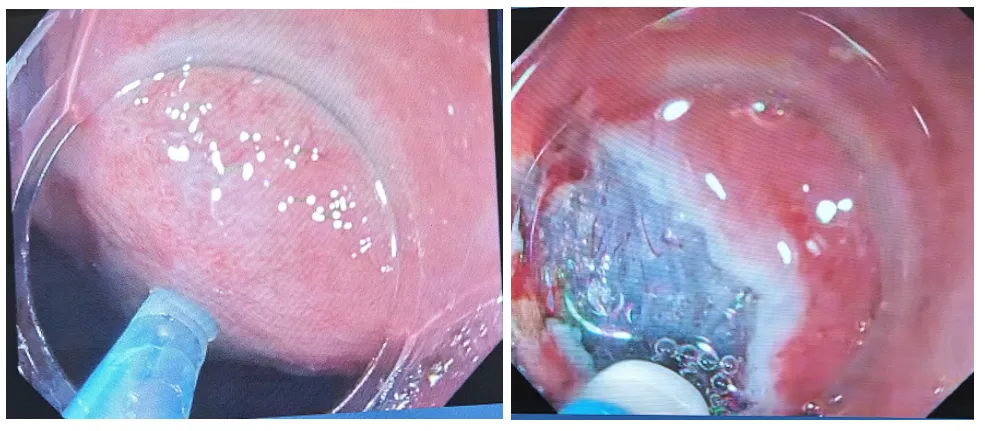

11:27完成病灶冲洗,吸引胃底体液体选用2.0mm的Dual刀,准备开始标记。标记时不用戴透明帽可以用强力电凝40-45W标记,个人习惯出刀头标记胃的病灶可以标得密集一点,宁多勿少;最后在口侧作双标记

11:35计划先在肛侧进行切开,胃角这个位置没有狭窄的风险,所以尽量切大一点粘膜下注射是生理盐水,导电好,对组织毁损小,可加点亚甲蓝或靛胭脂。

11:38,肛侧呈小“C”形浅开,再深切开深切开可以带凝尽量贴着固有肌层,要游离充分在肛门切开时胃内一直是打气的,口侧切开的时候则吸气口袋法(PCM)是不动肛侧,胃角两侧不切开要注意保持镜面的清洁,必要时要退出来清洁2014年前做胃角ESD是用牙线牵引法,现在令狐主委推隧道贯通法

病灶完整切下来了,对创面可疑的出血处给予电凝止血处理,无需缝合创面。

取出标本,复原固定标本后送检。